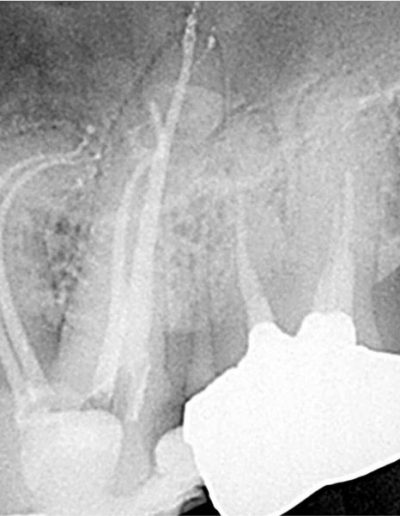

冠状の低侵襲アクセス。